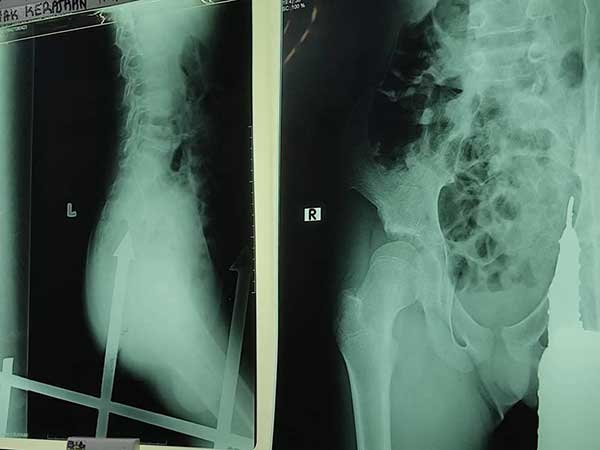

根据现场照片,刺入男童屁股的篱笆铁刺长约6寸,且刺中部位距离男童肛门只有毫米之差,目前暂不确定铁刺是否伤及男童体内器官。

据了解,该名男童送院急救后,已进行手术取出刺入屁股的篱笆铁刺,目前暂无生命危险。

12岁华裔男童趁母亲不在家时,竟攀爬篱笆铁门,孰料一失足导致臀部被篱笆刺中,伤口深约6寸,男童随后被送院急救。